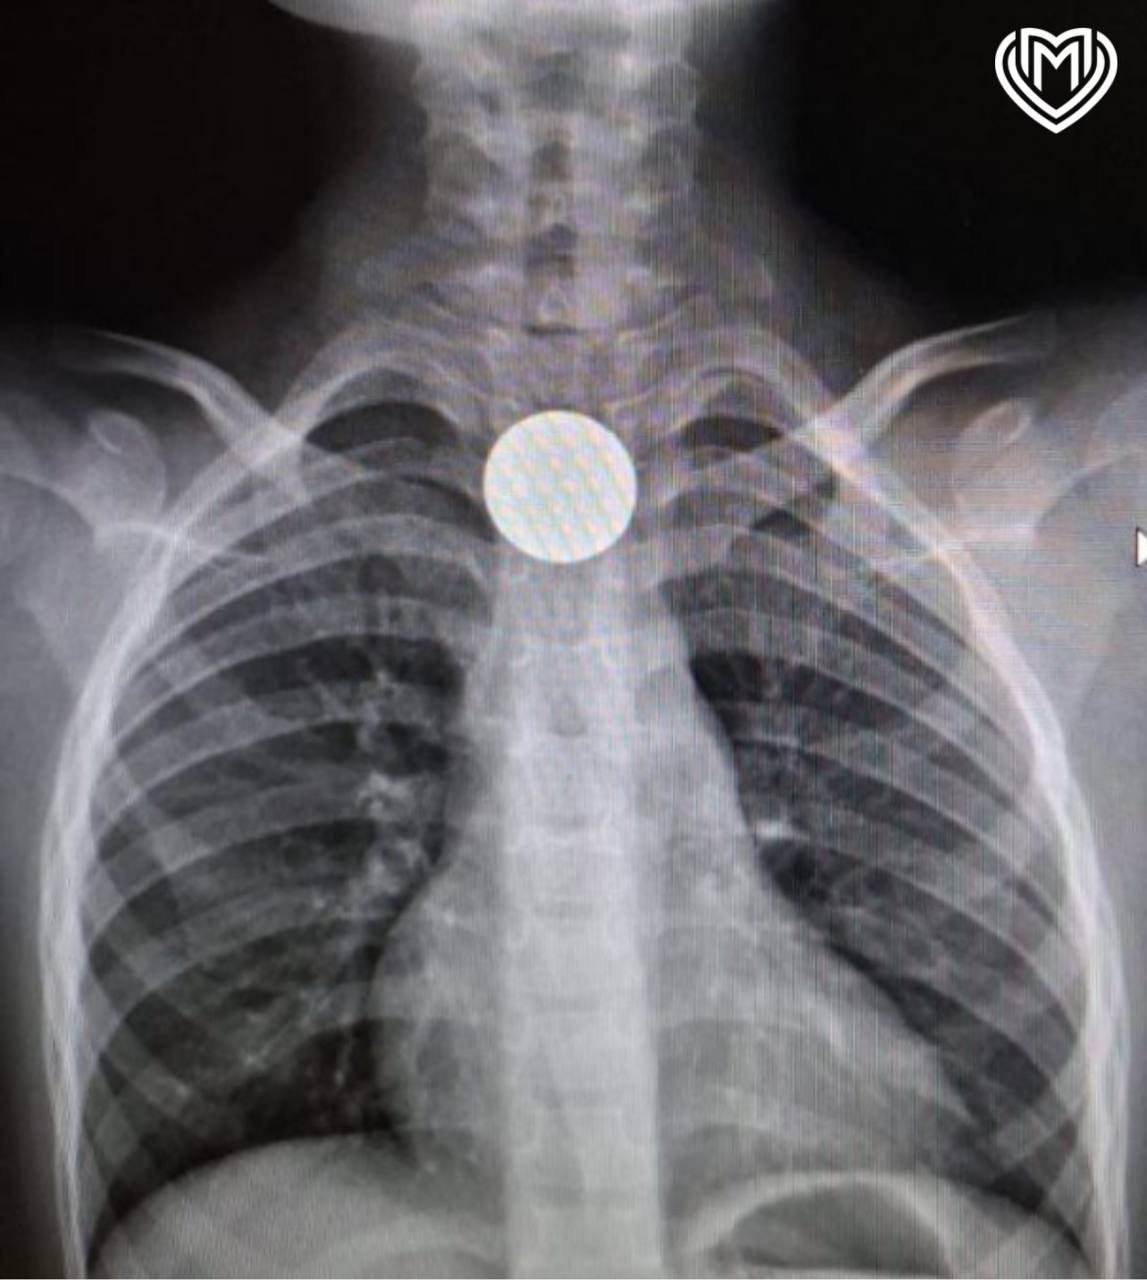

Ребенок проглотил рублевую монету

Ребенок проглотил рублевую монету 107 фото